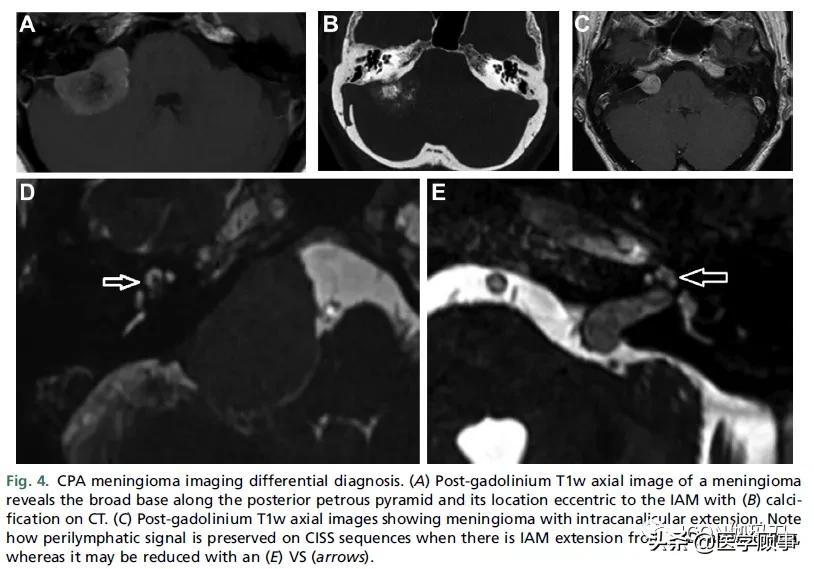

图4。CPA脑膜瘤影像学鉴别诊断。(A)钆剂后T1w轴位脑膜瘤图像显示沿岩锥体后部的宽基底,其位置相对IAM是偏心的; (B) CT上有钙化。(C)钆剂后T1w轴位图像显示脑膜瘤伴管内延伸。注意,当(D)脑膜瘤有IAM延伸时,CISS序列上淋巴管周围信号是如何被保留的,而(E) VS(箭头)周围的信号可能会减低。